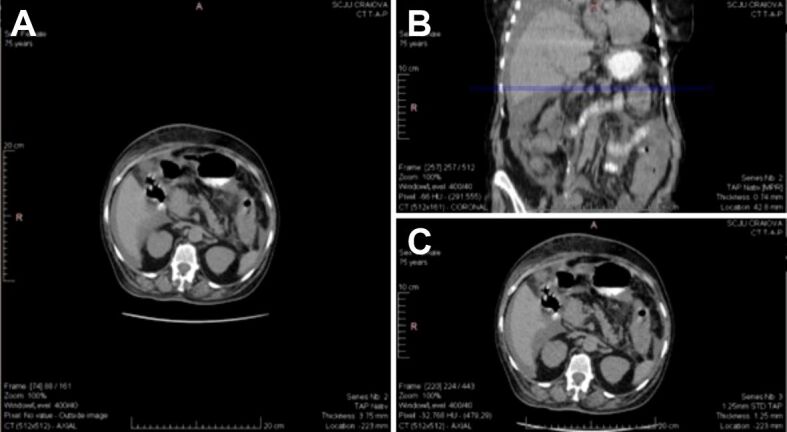

Abstract Image